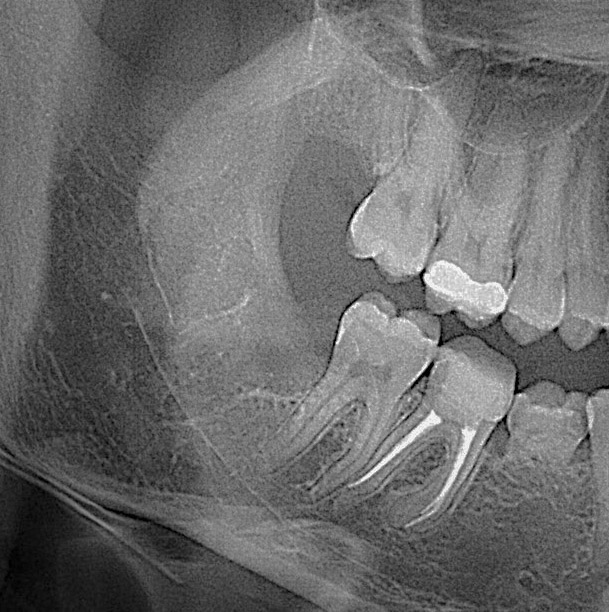

🦷 Зуби мудрості, 🎱 вісімки, часто викликають біль🤦 , запалення або тиснуть на сусідні зуби.😖 Їх видалення вимагає спеціальних навичок- і ми це вміємо. В АРТ Стоматології проводимо видалення зубів мудрості, будь якої складносі, яке можливо в амбулаторних умовах.

✅ 3Д планування та рентген диагностика

Первинний осмотр у стоматолога, рентгенологическое исследование, при наличии показаний принятие решения об удалении зуба мудрости.